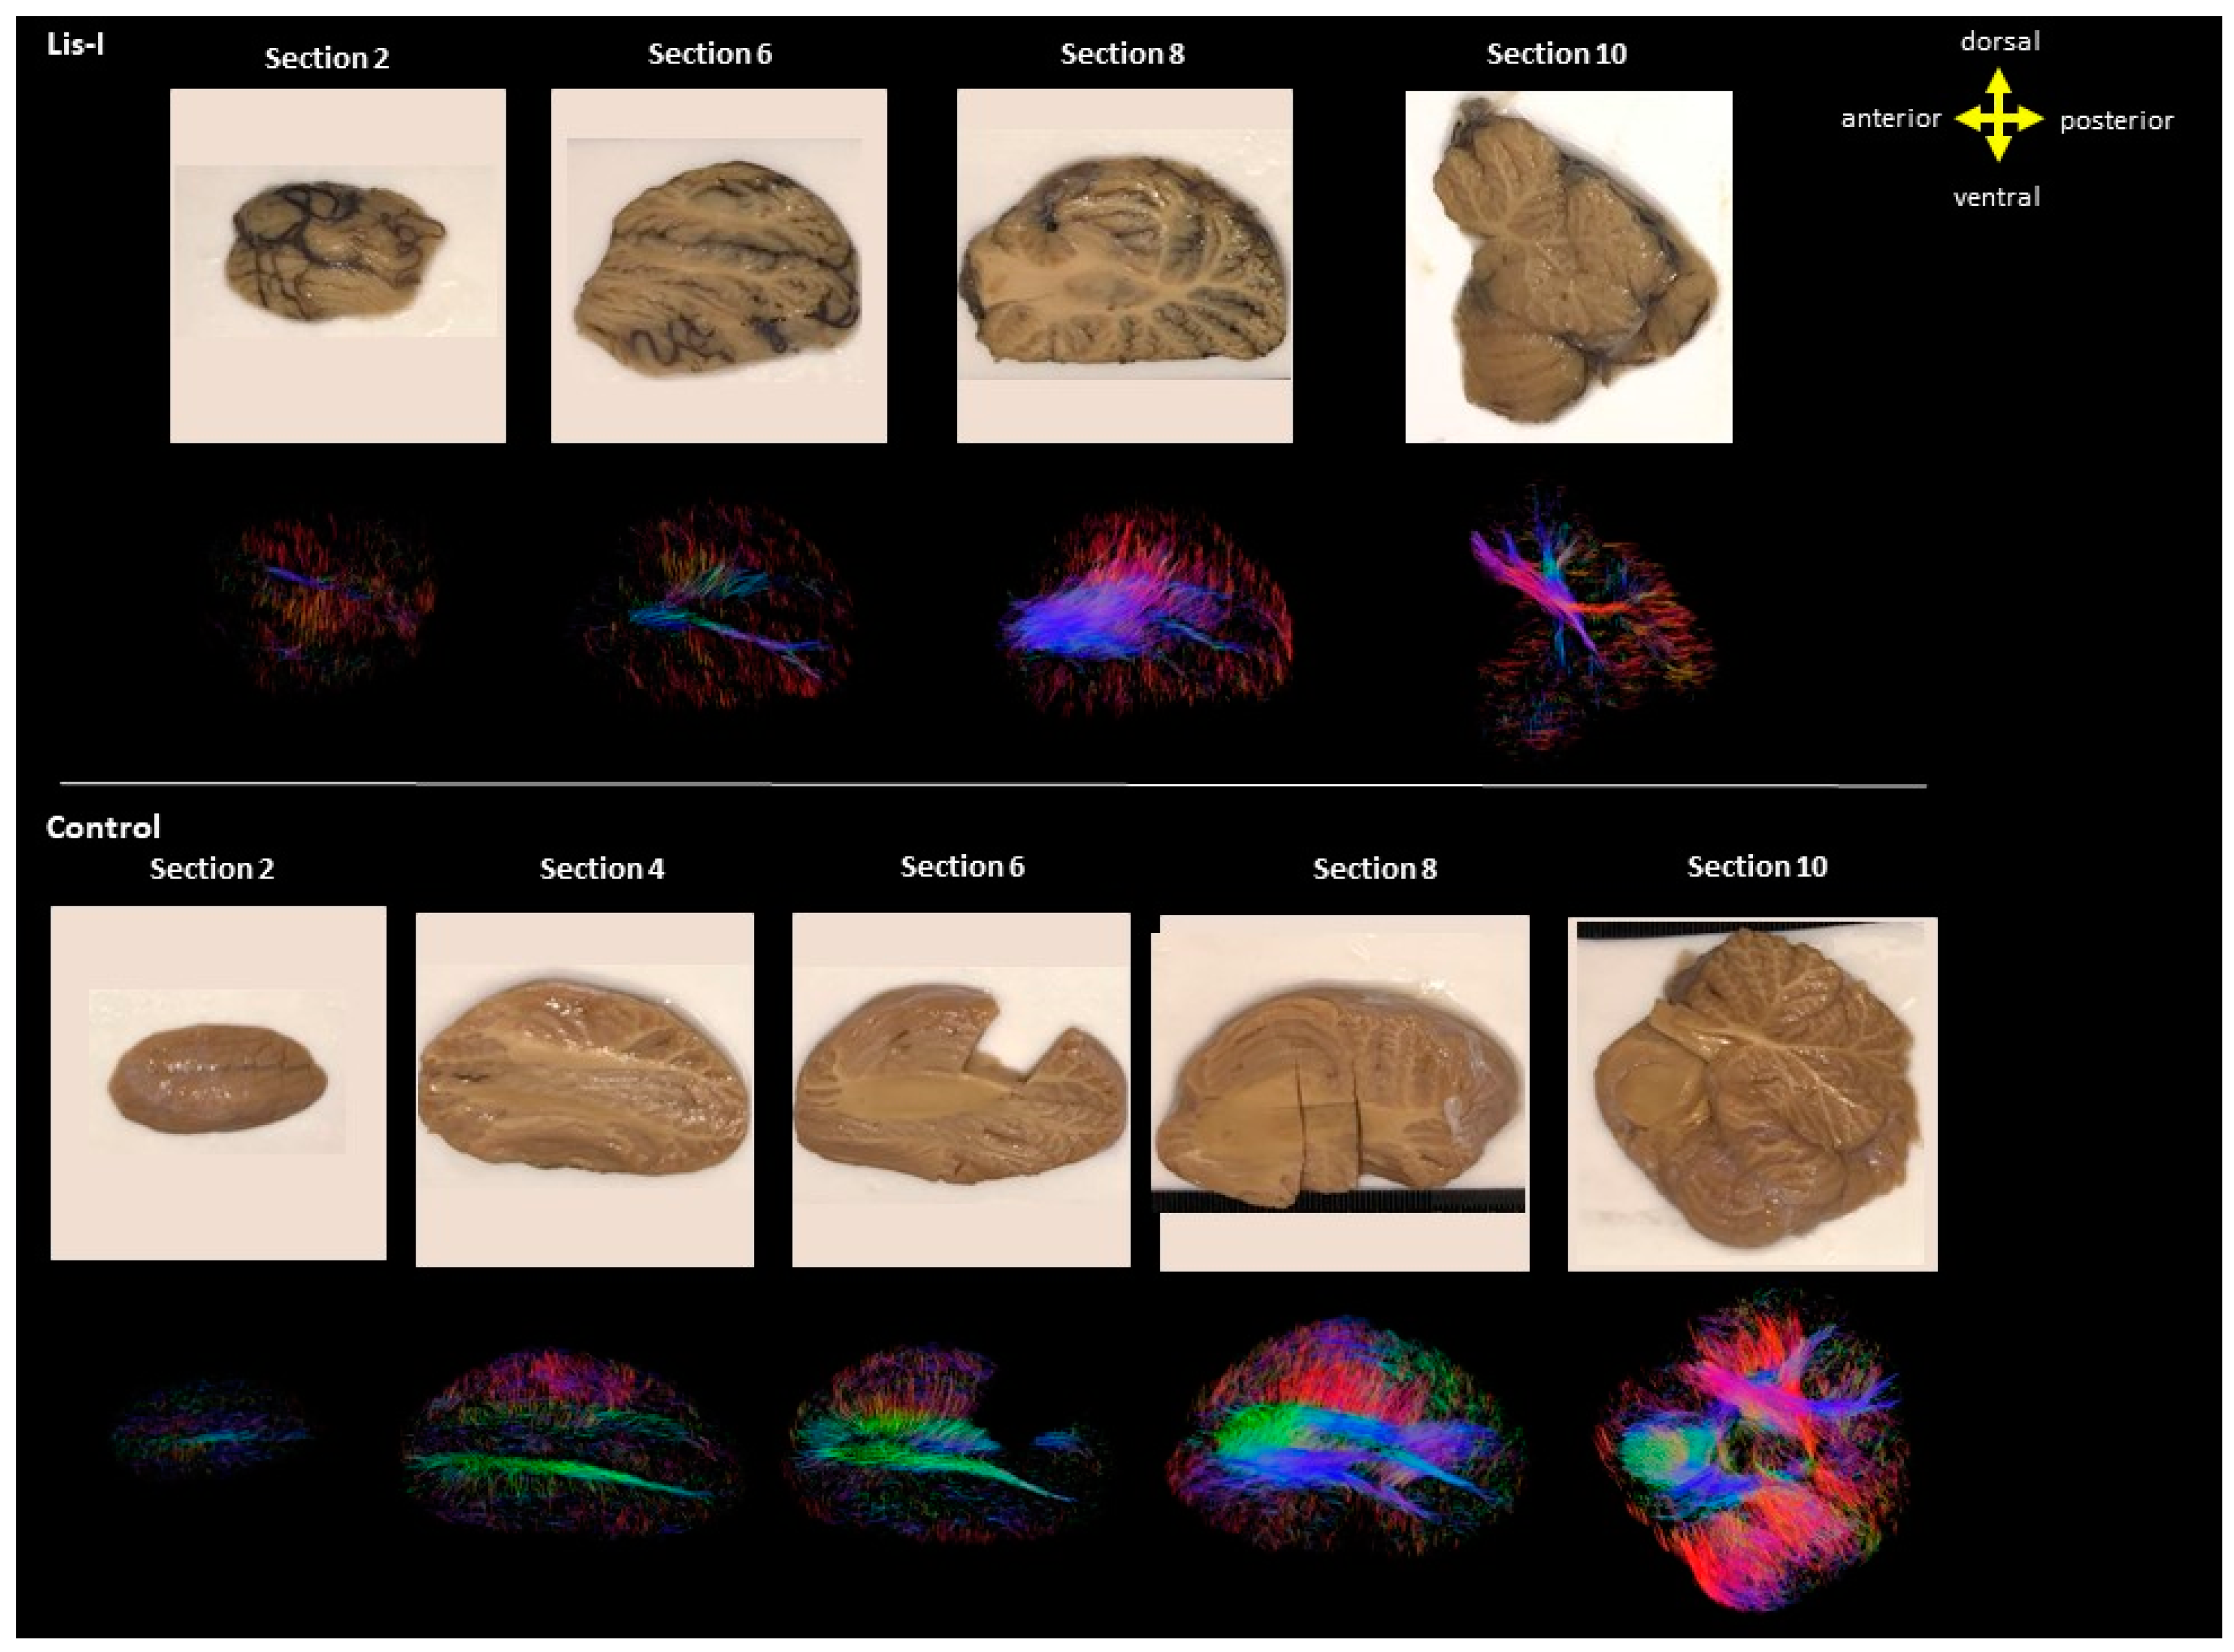

3. Results

4. Discussion

4.2. Microanatomy of Lissencephaly